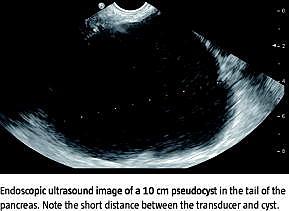

Pseudocyster i pancreas er væskeansamlinger, der er omgivet af en kapsel bestående af granulationsvæv og fibrøst væv. De opstår som komplikation til akut eller kronisk pancreatitis. De fleste pseudocyster er små og forsvinder uden behandling. Der er indikation for behandling, hvis en pseudocyste persisterer og giver symptomer. Perkutan aspiration er en ofte benyttet behandlingsform, men recidivraten er høj. Endoskopisk transmural drænage er en minimalt invasiv behandlingsform, hvorved der indsættes en stent mellem pseudocysten og mave-tarm-kanalens lumen. For at øge sikkerheden sker indsættelsen af stenten under vejledning af endoskopisk ultralyd (EUS).

Alle de 22 patienter, der fik udført en EUS-vejledt drænage af pseudocyster i pancreas i perioden fra december 2005 til august 2010 på Gentofte Hospital, blev inkluderet (middelalder 51 år, 13 mænd). Den gennemsnitlige cystediameter var 8,1 cm (spændvidde 3,8-18 cm). En eller to 10 fr. dobbelte grisehalestenter blev indsat i pseudocysten enten fra ventriklen eller fra duodenum. Patientdata blev fundet ved søgning på procedurekoder. Alle procedurebeskrivelser, henvisninger og journalnotater blev gennemgået.